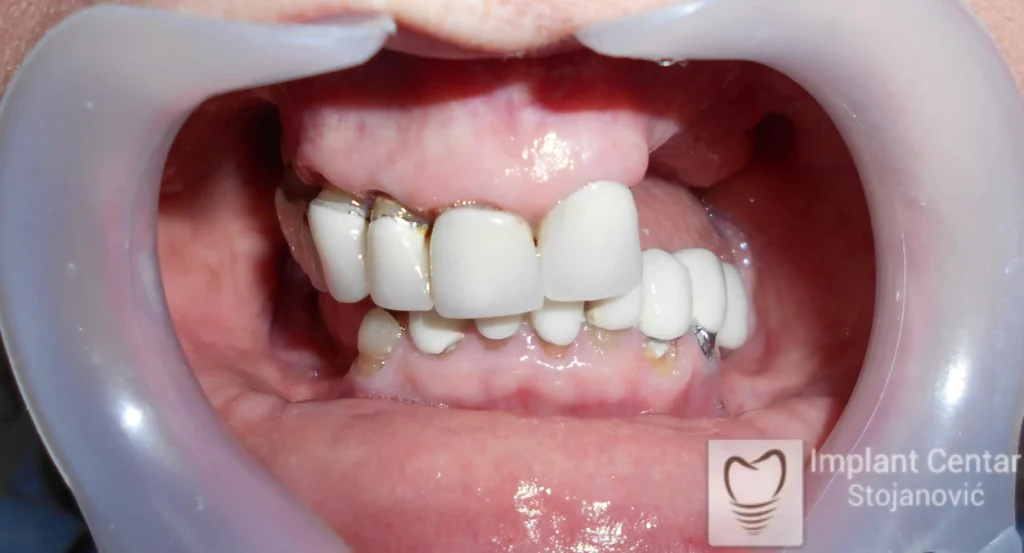

Na slici 1. i slici 2. prikazan je izgled pacijenta pre početka terapije – klinički i rendgenološki.

Nakon vađenja zuba, ugrađeni su implantati. Na slici 3 prikazan je ortopan snimak sa ugrđenim implantatima. Tokom perioda osteointegracije, pacijent je bio zbrinut fiksnim privremenim krunicama na implantatima, koje su izrađene samo dva dana nakon hirurške intervencije.

Na slikama 5. i 6. prikazan je izgled definitivnih cirkonijum-keramičkih mostova na implantatima.